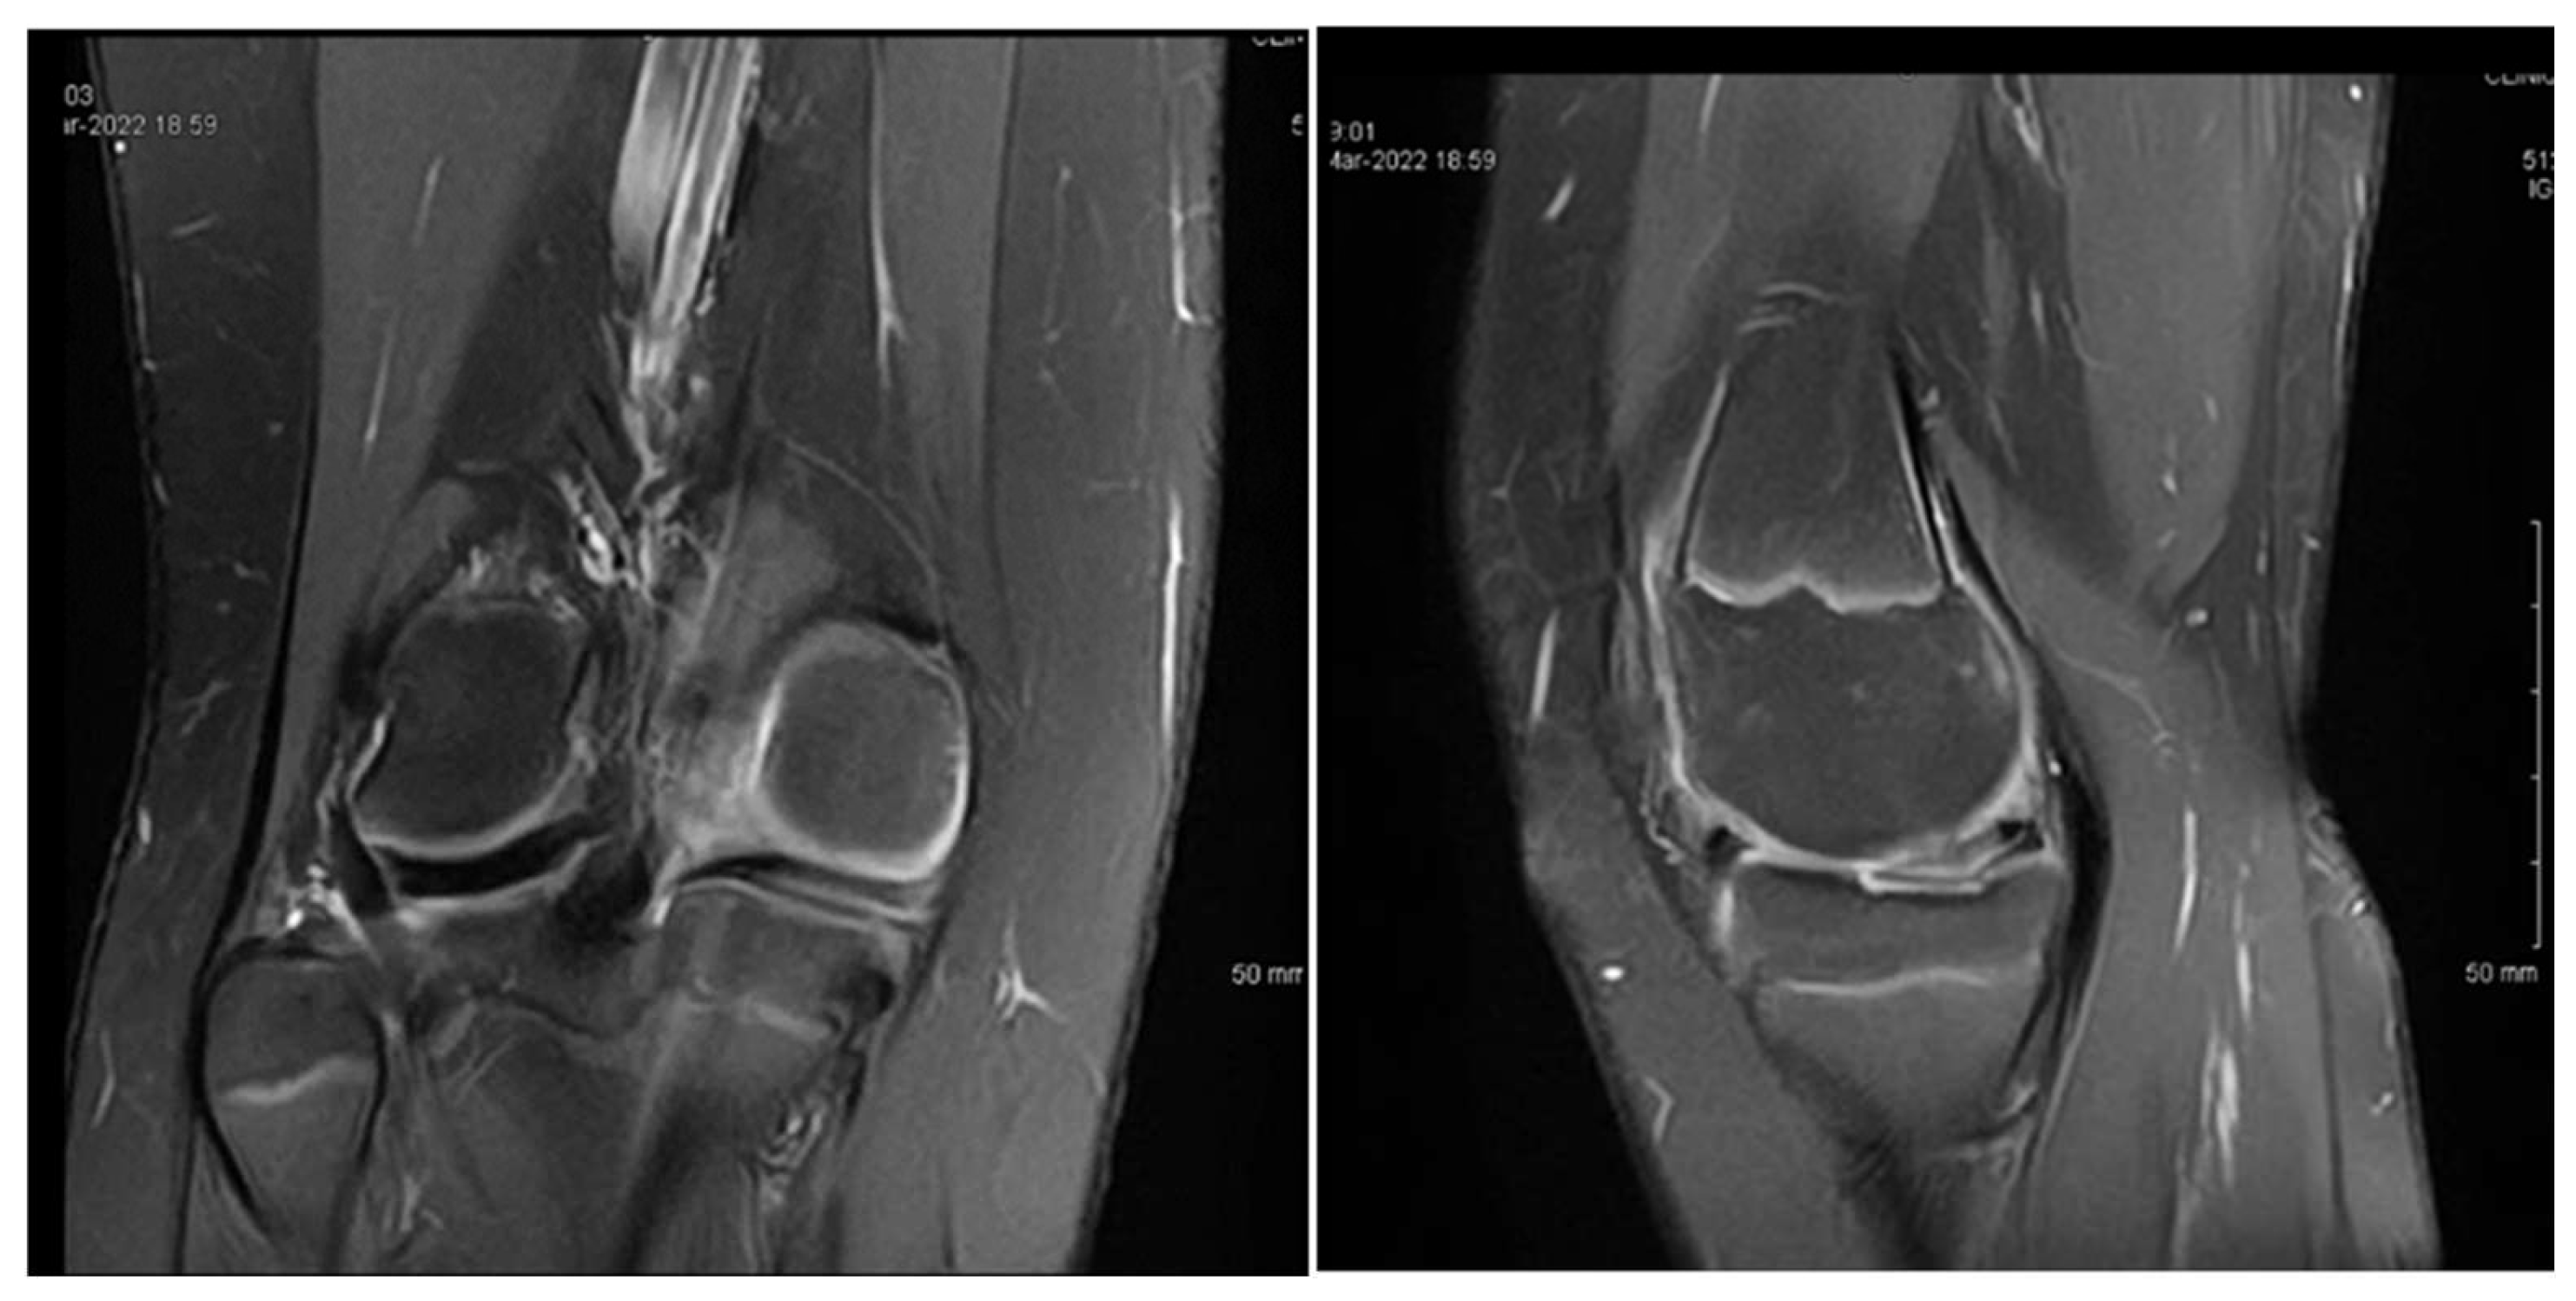

3.1. Case 1—P.E.

3.2. Case 2—S.C.S.

3.3. Case 3—G.L.